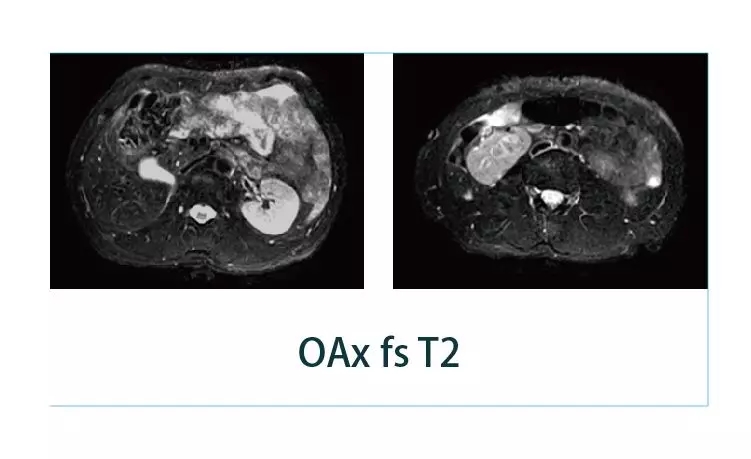

【朗润影像档案】20190329磁共振影像病例结果讨论

【朗润影像档案】磁共振影像病例分享(编号20190329)